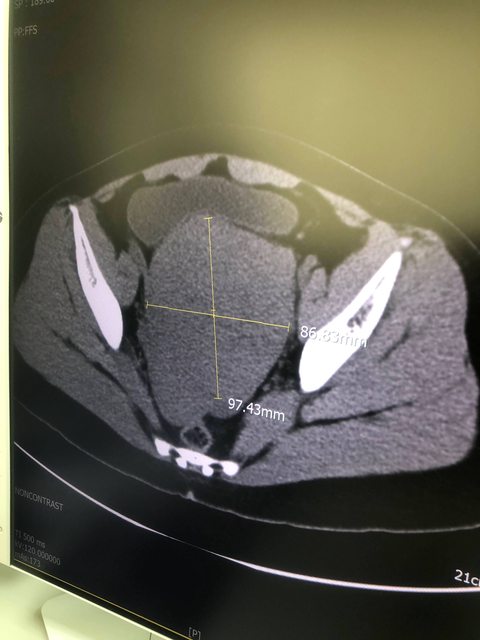

3/16到部立醫院看診後,蔡永隆醫生看到轉診單立即安排照超音波,照超音波時告知肌瘤已經大到9公分(我子宮原始內徑為7公分),是需要開刀的尺寸。

https://i.imgur.com/pedJOLN.jpg